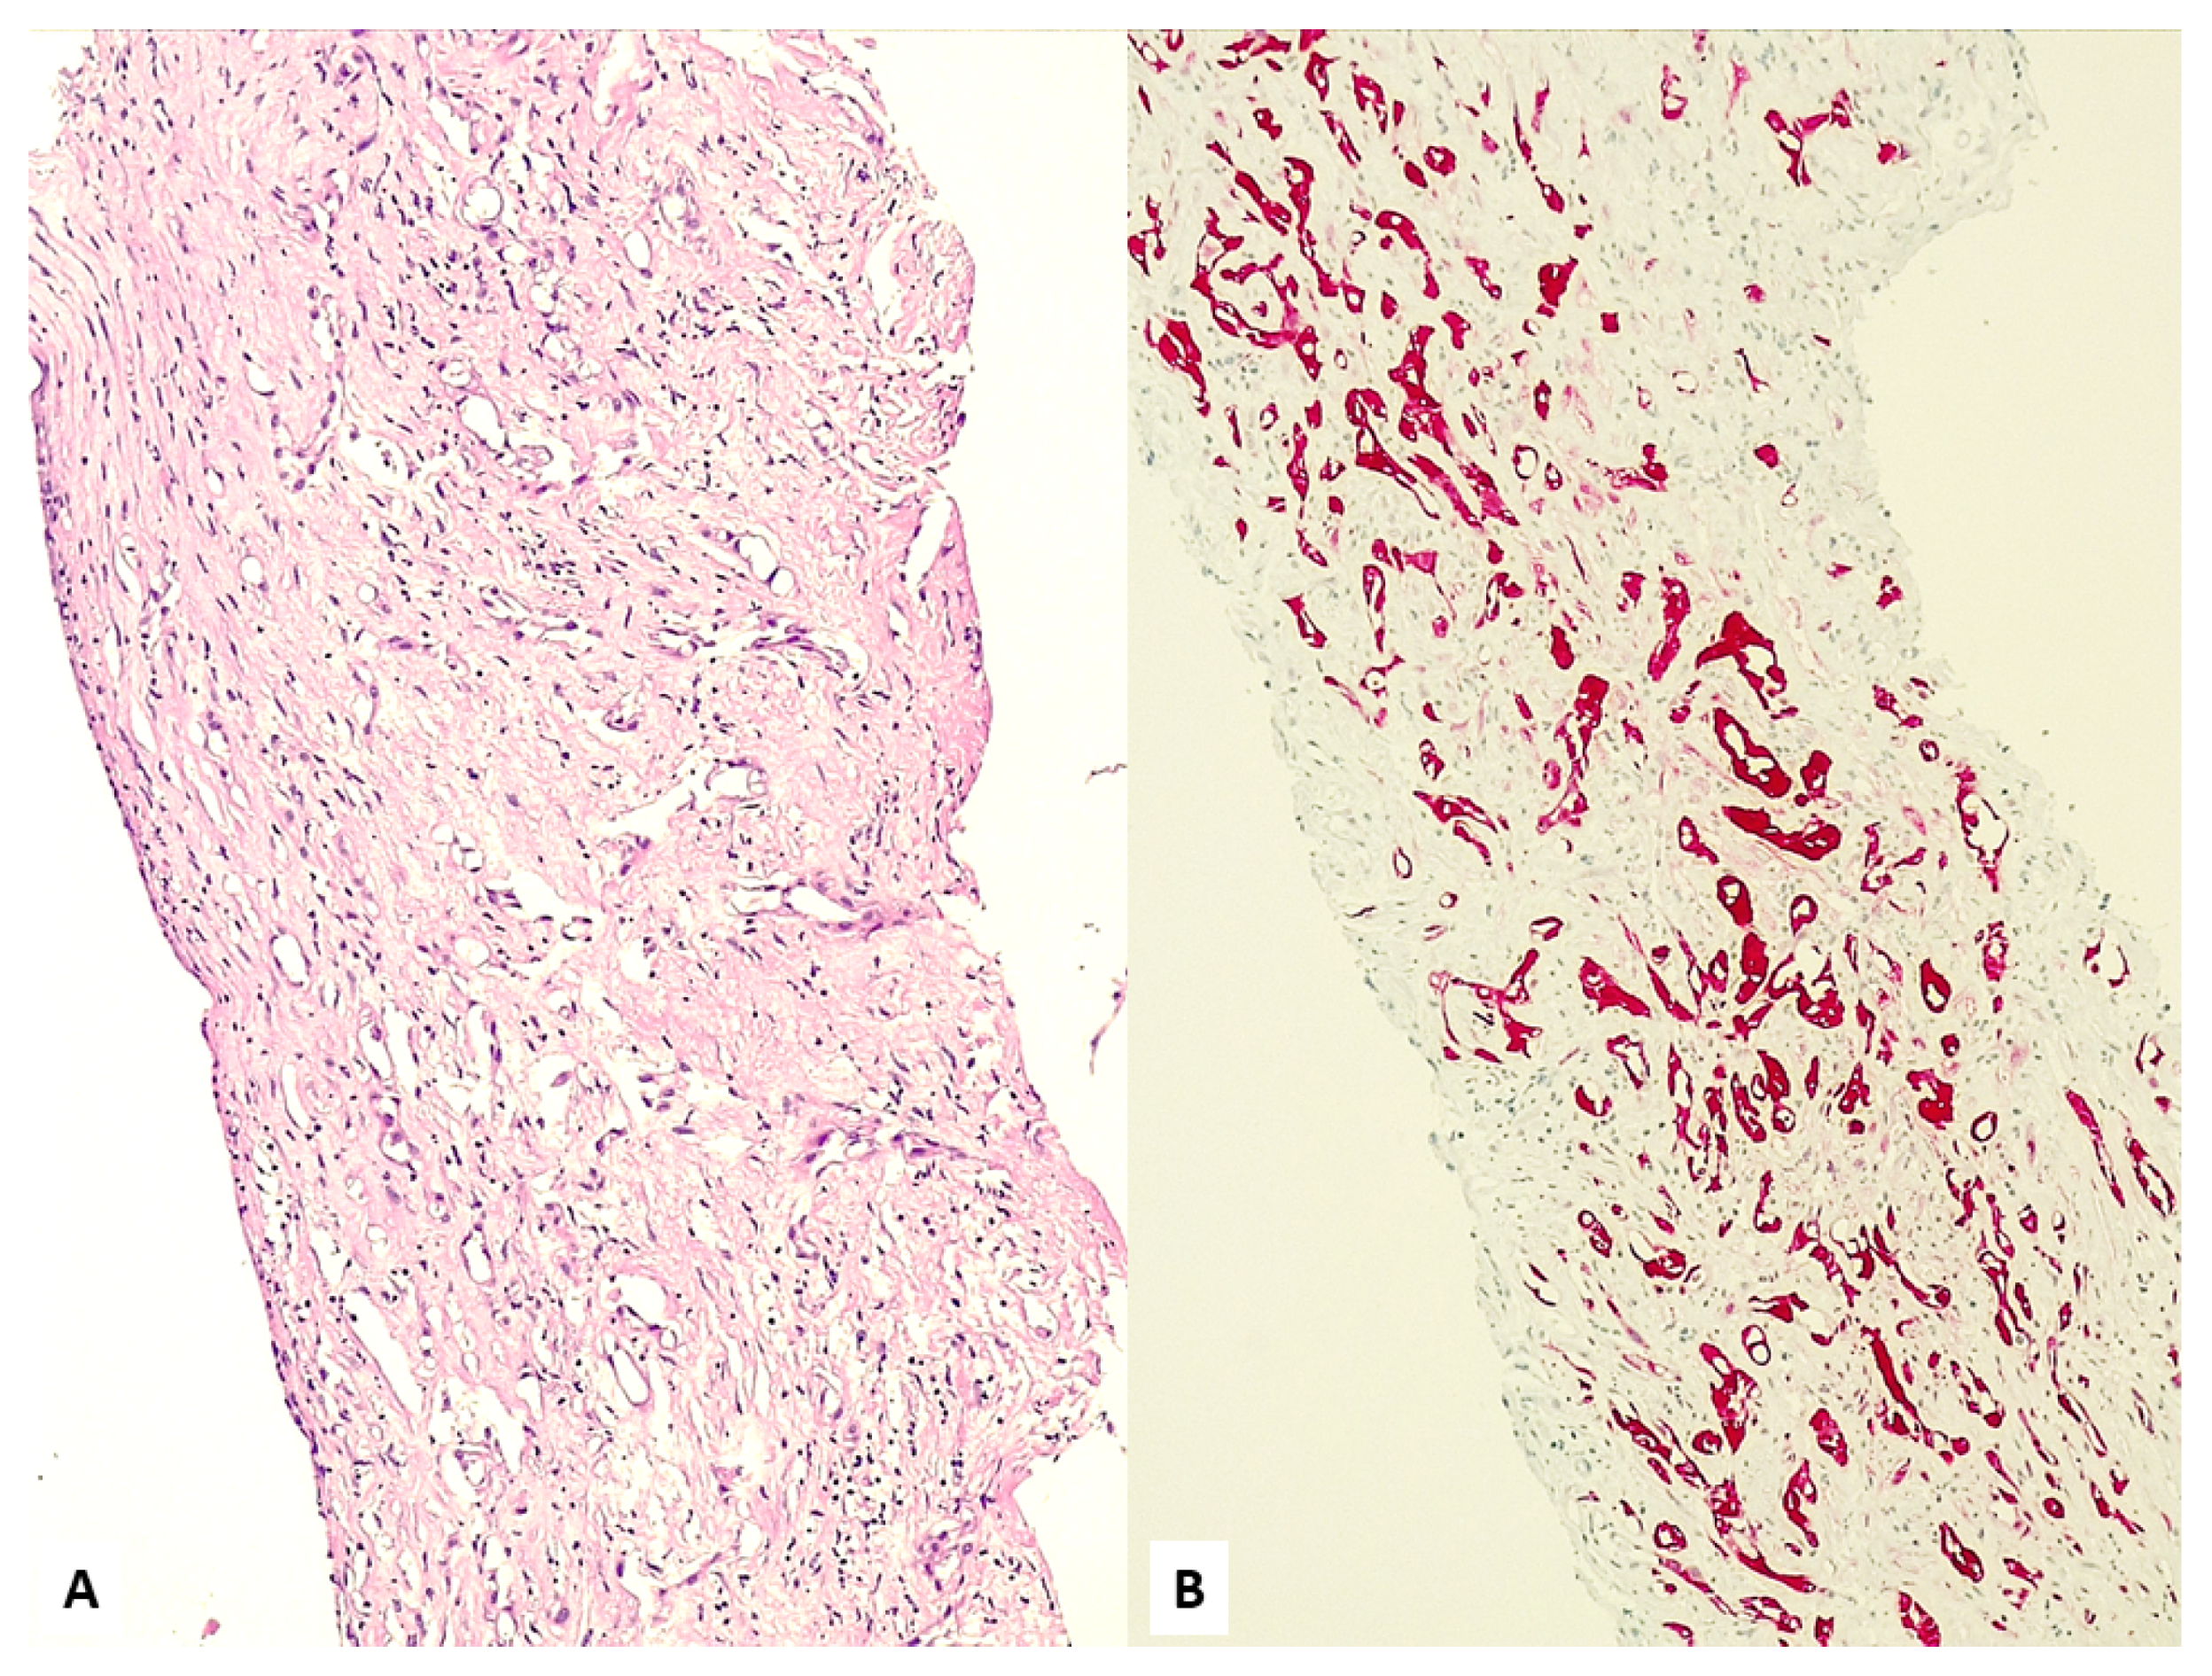

4. Unusual Morphologic and Immunohistochemical Features